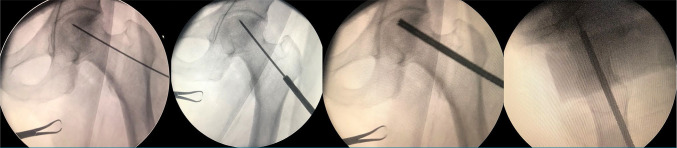

Patients and methods: Between February 2015 and February 2020, a total of 63 patients (45 males, 18 females; mean age: 45.8±11.7 years; range, 21 to 65 years) with early-stage AVNFH (Ficat-Arlet Stages I-II) who underwent treatment were retrospectively analyzed. The patients were divided into two groups: those treated with CD and grafting (CD+grafting; n=32) and those receiving additional PRF augmentation (CD+grafting+PRF; n=31). Demographic characteristics, including age, sex, and affected side, were comparable between the groups. Clinical assessments included pre- and postoperative Visual Analog Scale (VAS) for pain, Harris Hip Score (HHS), and Merle d'Aubigné Hip Score.